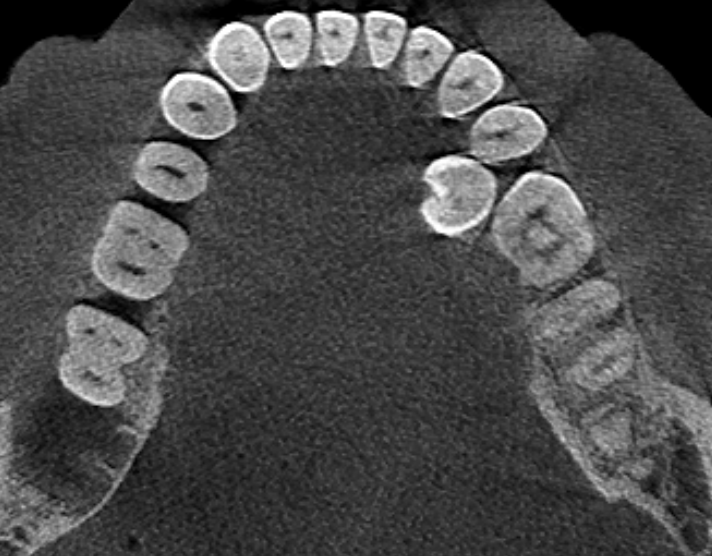

Александр9 Опубликовано 26 ноября, 2021 Поделиться Опубликовано 26 ноября, 2021 Мне предлагают удалить дистопированный 35 зуб, но он мне не мешает. Меня только пугает, что из-за него "страдают" соседние зубы. И если его не удалить, то со временем придется удалять и их. Подскажите пожалуйста, оправданно ли его удаление с целью улучшения "жизни" соседних 34, 36 зубов? (при условии нормальной гигиены (ирригатор, зубные нити) и лечении кариеса). Ссылка на комментарий